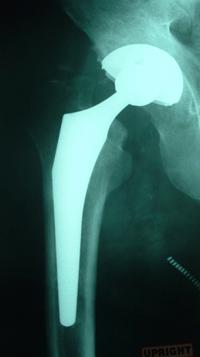

Once in the operating room, the old, damaged hip is removed.  The new parts, made of titanium, cobalt chromium, and other super metal alloys, as well as ceramic and/or high density polyethylene type plastics, are carefully fit for size and position.

Some are cemented in place while most are press-fit, a newer technique.